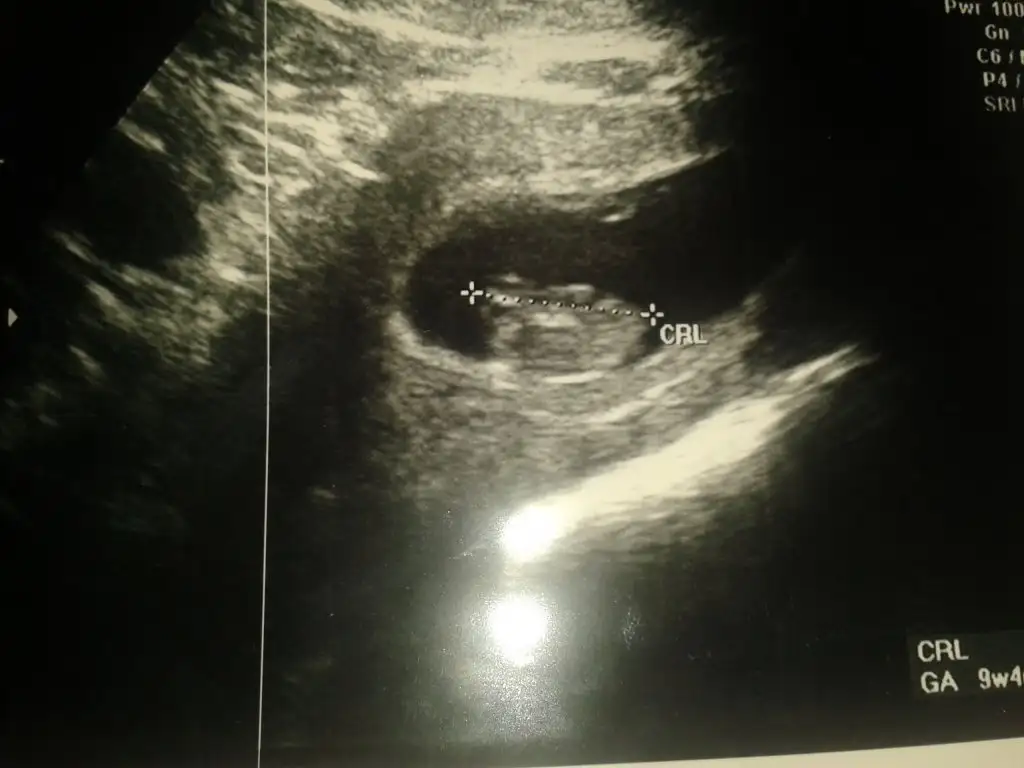

Erkek bence yalniz nub icin erkek annesi 12 . Haftayi bekleKızlar sizce nedirEki Görüntüle 1535231

Dr birşey söylemedimi pekiKizlar 12+4 haftalikmis bebegim bakarmisiniz acaba tahminleriniz nedir ben anlayamadim

yorum yaparmısınız arkadaşlar .iki yeni resim daha yükledim lütfen yorumlarınızı bekliyorum

20 haftalığım bende hala öğrenemeynlerdenim .yorum yaparmısınız arkadaşlar .